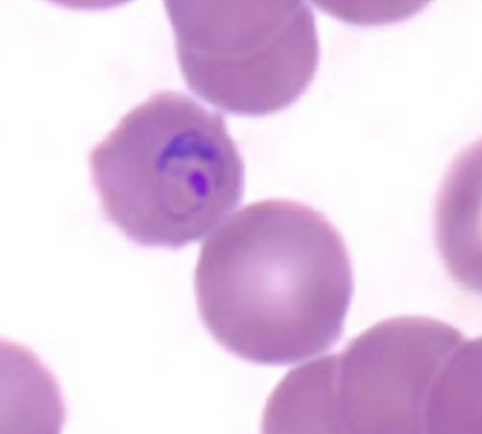

Plasmodium malariae

Plasmodium malariae